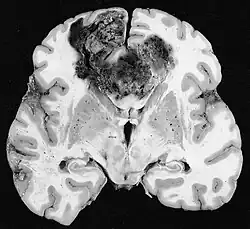

Glioblastoma

Os tumores de células gliais mais comuns e malignos são os glioblastomas. Consistem em uma massa heterogênea de células de astrocitoma pouco diferenciadas principalmente em adultos. Geralmente ocorrem nos hemisférios cerebrais, mais raramente no tronco cerebral ou na medula espinhal. Exceto em casos muito raros, como todos os tumores cerebrais, eles não se estendem além das estruturas do sistema nervoso central.

O glioblastoma pode surgir de uma forma difusa (II. grau) ou um astrocitoma anaplásico (III. grau) se desenvolvem. Neste último caso, é chamado de secundário. No entanto, quando ocorre sem antecedentes ou evidência de malignidade prévia, é referido como primário. Os glioblastomas são tratados com cirurgia, radioterapia e quimioterapia. Eles são difíceis de curar e há poucos casos que sobrevivem além de três anos.

Na ressonância magnética, um tumor intracraniano aparece como uma lesão maciça que pode se tornar mais luminescente após o uso do agente de contraste. No entanto, há sempre uma anomalia de sinal na ressonância magnética, que indica a presença de neoplasia ou edema vasogênico. Normalmente, o aumento da luminescência (realce pelo contraste) é indicativo de um tumor de grau mais alto de malignidade. Um anel contrastante é característico do glioblastoma, com a porção luminescente correspondendo à parte vital do tumor maligno e a área mais escura-hipointense à necrose tecidual.